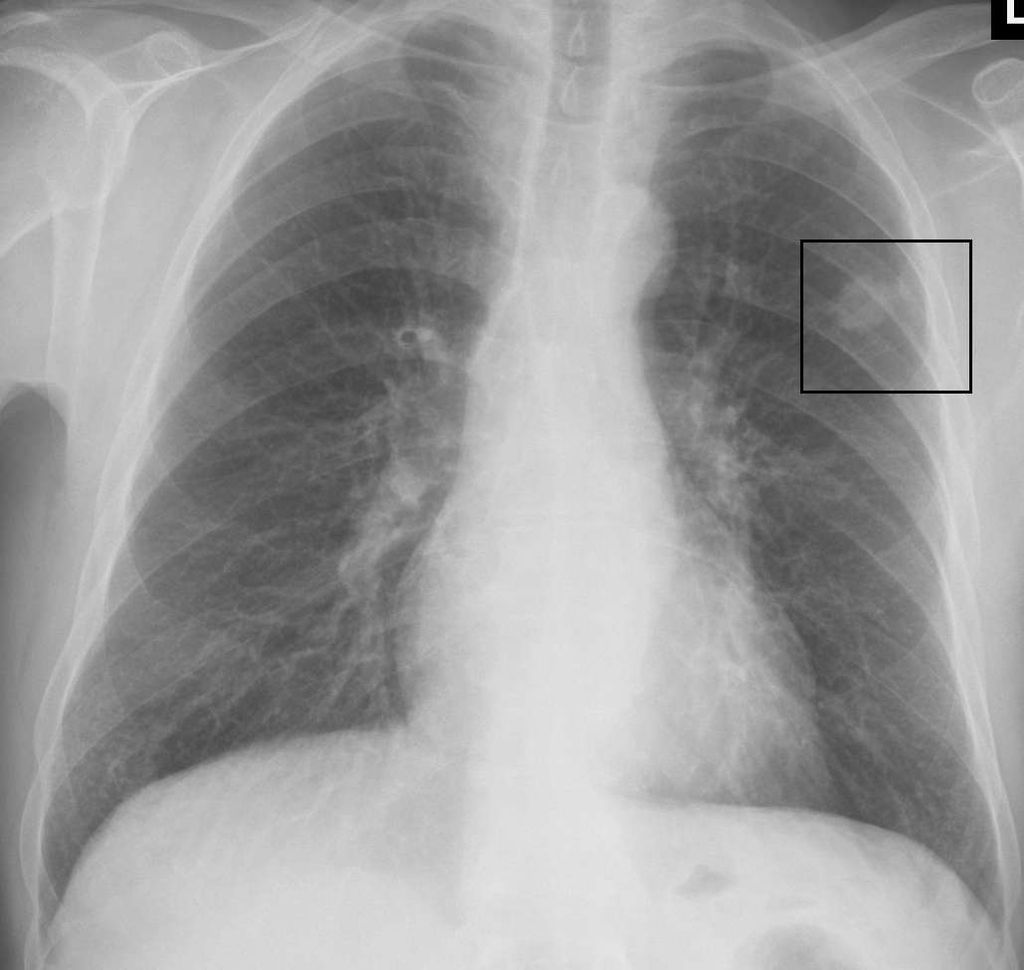

Bildgebung

• Röntgen-Thorax bzw. CT-Thorax zum Nachweis der Raumforderung,

• CT bzw. MRT Abdomen, MRT Schädel und Knochenszintigraphie (alternativ PET-CT besonders bei kurativem Ansatz) zum Ausschluss einer Organmetastasierung